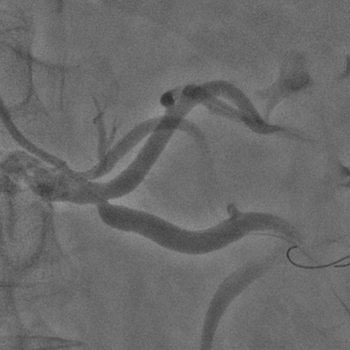

Бифуркационное стентирование почечной артерии

Ангиографическое исследование аорты и селективная ангиография сосудов почек выявило критический стеноз a. segmenti inferioris и короткую a. renalis sinistra